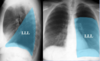

110

Case Study: 30yo female with 1 week of fever and cough

* Right Middle Lobe Pneumonia * Left Upper Lobe Pneumonia

111